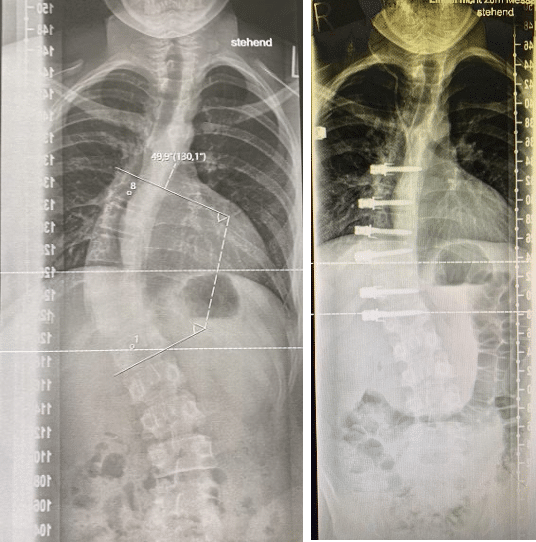

X-ray images of patient with a lumbo-thoracic scoliosis with a 50º angle before surgery (image on the left) compared to the X-ray image after ASC surgery showing a corrected spine with an angle of 20º (image on the right). The patient’s growth will end up reducing the small remaining curve and straighten out the spine.